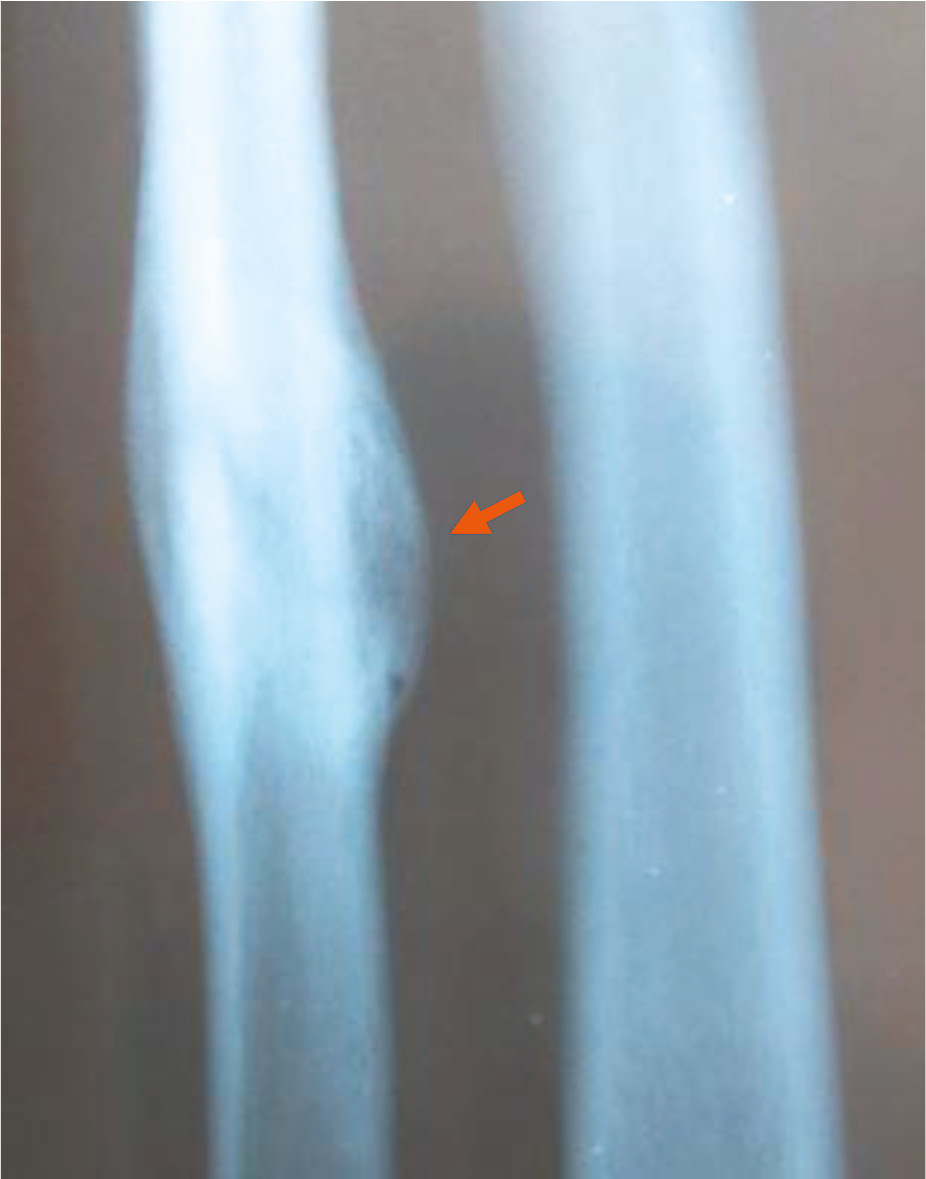

6) 91–120 суток (3–4 месяца): линия перелома постепенно теряет свою чёткость и ясность, у 67% мужчин и 33% женщин прослеживается на всём протяжении, у 17% мужчин видна на 2/3, у 17% мужчин ― на 1/2 всей протяжённости; края перелома остаются сглаженными, концы отломков закруглённые; костная мозоль уплотняется: у 33% мужчин она равна плотности губчатого вещества, имеет чёткие, ровные границы, у 67% мужчин интенсивность костной мозоли соответствует плотности кортикального слоя, при этом у 17% она не имеет чётких границ, а у 50% мужчин и 33% женщин ― с чёткими, ровными границами (см. табл. 3 и 4; рис. 1);

Рис. 1. Перелом диафиза локтевой кости давностью 4 месяца (стрелка): линия перелома просматривается нечётко, костная мозоль неравномерной плотности с чёткими, относительно ровными границами.

Fig. 1. Fracture of the diaphysis of the ulna, 4 months old (arrow): the fracture line is not clearly visible, the callus is of uneven density, with clear, relatively smooth boundaries.